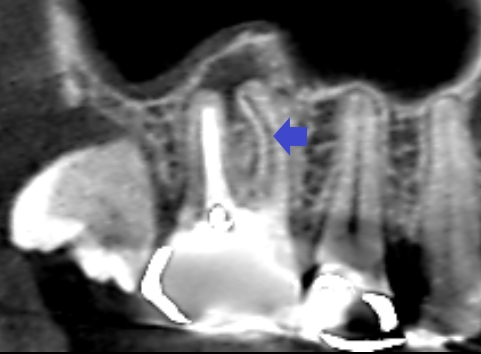

6カ月後の経過観察時のCT画像です。矢印の先にあった膿の影が消え、歯槽骨が再生しています。